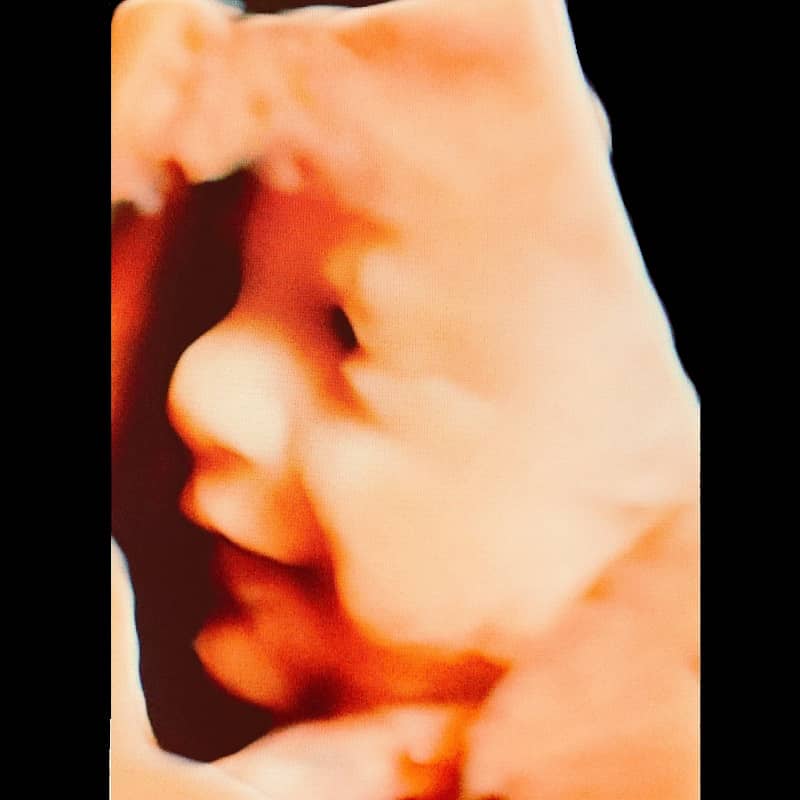

Kliniğimizde yapılan ayrıntılı ultrason muayenelerinden 4 boyutlu ultrason örnekleri:

3 boyutlu renkli ultrasonda derinliği de yansıtan üç boyutlu bir görüntü vardır. Bebek renkli olarak görüntülenir. 2 boyutlu ultrasona göre daha net ve belirgin bir görüntü vardır.

4 boyutlu ultrason (4D ultrason) görüntü özellikleri açısından 3 boyutlu ultrasona benzer. 4 boyutlu ultrasonun farkı hareketli olmasıdır. Bir anlamda anne karnındaki bebeğin video görüntüsüdür.